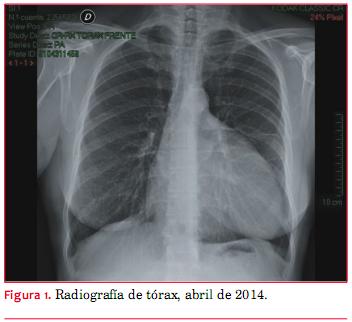

Paciente de 58 años, sexo femenino. Fumadora de 20 cigarrillos diarios, sin otros antecedentes a destacar. Concurre a una revisión médica de rutina, sin síntomas relevantes en el área cardiovascular y con un examen físico normal. Como parte de su evaluación se realiza una radiografía de tórax de frente (figura 1) en la que se observa un masivo aumento de la silueta cardíaca con densidad heterogénea, a expensas de un borde izquierdo convexo, que alcanza la región axilar y se aproxima al ángulo costo-frénico izquierdo. Los campos pulmonares son normales y las marcas vasculares también son normales.

La paciente aporta otra radiografía realizada 18 meses antes (figura 2) en la que la silueta cardíaca también estaba aumentada, con un aspecto más globuloso, pero en una magnitud mucho menor a la observada en el momento de la consulta. En ambas radiografías se sospecha una masa ovoidea de distinta densidad, sobreimpuesta al borde izquierdo de la verdadera silueta del corazón.

Hemos presentado el caso de una paciente asintomática con el hallazgo de un marcado incremento de la silueta cardíaca en una radiografía de tórax. El ecocardiograma mostró una extensa colección líquida paracardíaca y la tomografía de tórax mostró un voluminoso quiste de mediastino anterior, que se extendía desde encima del cayado aórtico hasta la proximidad del ángulo costo-frénico izquierdo.